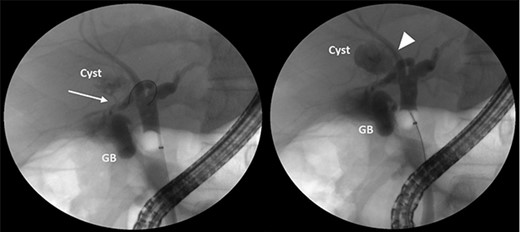

A 35-year-old man presented with a history of recurrent episodes of epigastric pain. Ultrasonography revealed an intrahepatic cyst (Fig. 1), and magnetic resonance cholangiography revealed that the cyst was connected to the cystic duct and right anterior sectoral bile duct (Fig. 2). The patient underwent an endoscopic retrograde cholangiography, which showed that the contrast could fill the cyst (Fig. 3). The laboratory findings, including a complete blood count, showed a white blood cell count of 4200/mm3 (lymphocyte 23%, neutrophil 62%); haemoglobin level of 16 g/dL; platelet count of 215 × 103/ mm3; total protein of 7.8 g/dL; albumin of 4.3 g/dL; total bilirubin level of 0.68 mg/dL; serum aspartate aminotransferase level of 26 IU/L; serum alanine aminotransferase level of 29 IU/L and alkaline phosphatase level of 105 IU/L. Tumour markers, including alpha-fetoprotein, carcinoembryonic antigen and carbohydrate antigen 19–9 were within normal limits. Viral markers for hepatitis B and C were negative. Due to the preoperative diagnosis of a type VI choledochal cyst, with a differential diagnosis of cystic intraductal papillary neoplasm of the bile duct, the patient underwent laparoscopic right anterior sectorectomy to excise the cyst completely. During the operation, after identifying the cystic duct and taking down the fundus and body of the gallbladder from the liver bed, an intraoperative cholangiogram was performed via the cystic duct connected to the cyst. Right anterior sectorectomy was then performed (Fig. 4). The postoperative period was unremarkable, and the patient was discharged on the sixth postoperative day. Pathological examination revealed a cyst with a fibrous wall, dense chronic inflammatory infiltration, lined by columnar epithelium. Mild reactive atypia, associated with marked chronic inflammatory cell infiltration, was noted. No signs of epithelial dysplasia were observed (Fig. 5).

ERCP showing that the cyst can be filled with contrast from the cystic duct (arrow) and the right anterior sectoral bile duct (arrowhead).